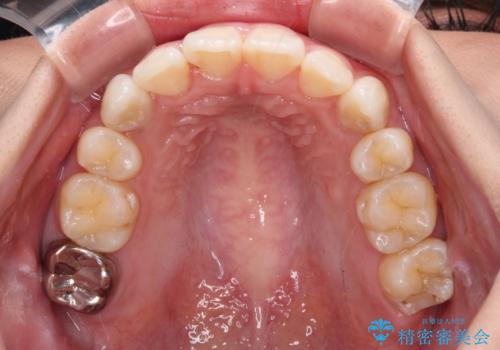

上顎の八重歯と下顎前歯の欠損 ワイヤー装置による抜歯矯正

下顎前歯と本来抜歯矯正で抜歯する歯とは大きさが異なるため、仕上がりの咬み合わせは理想的なものとはなりませんでしたが、気になっていた八重歯はきれいに改善することができました。